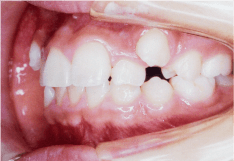

- 開咬(かいこう)

- 噛んでいても前歯がかみ合っていない状態のことで、発音が悪くなったり、前歯でものを噛み切ることが難しくなります。舌の癖や指をしゃぶる癖が原因で起こることがあります。